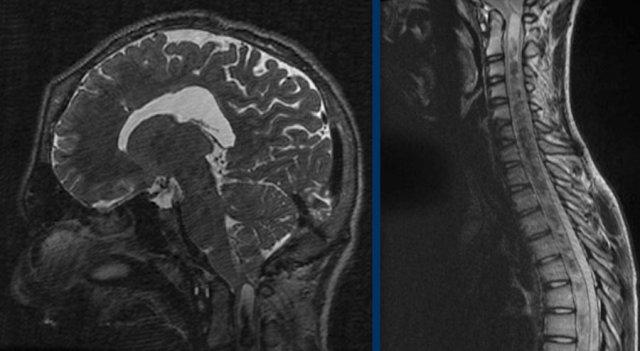

Dị tật Chiari có thể gây rỗng tủy sống.

Các hình ảnh thuộc về một bệnh nhân có tăng áp lực nội sọ.

Có hình ảnh thoát vị hạnh nhân tiểu não với tình trạng chèn ép nặng tại vùng nối sọ-cổ.

Hậu quả là hình thành ổ rỗng tủy trải dài toàn bộ chiều dài của tủy sống.